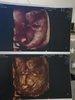

To i ja zamelduję tutaj o wczorajszym badaniu. Bąbelek ma 5,6 cm, wielkość zgadza się z OM, czyli 11+6. Strasznie się wiercił, ciężko było złapać cokolwiek

. Cudownie to wyglądało jak co chwila nawiewał przed sondą